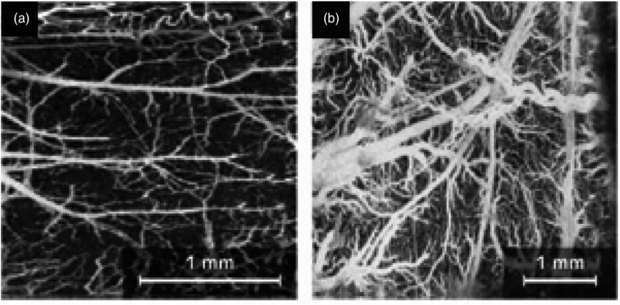

Second-generation OCT systems, known as Fourier (frequency) domain OCT, are now available including the Thorlabs Spectral Radar OCT imaging system (Newton, NJ, USA). Frequency domain techniques have several advantages over time domain systems including a higher sensitivity and speed. The improved speed allows for rapid cross sectional image collection, enabling facile imaging of larger sample volumes in real-time. Additional contrast mechanisms are able to extend the capability of OCT. Doppler OCT or optical Doppler tomography is one kind of functional extension of OCT which combines the Doppler principle with OCT and provides in-vivo functional imaging of moving samples, flows and moving constituents in biological tissues (Liu 2012) (figure 21).

Figure 21. Doppler OCT imaging: (a) microvasculature of a mouse cerebral cortex and (b) microvasculature of a rat cerebral cortex. Scale bars are shown (permission granted to re-use from Liu and Chen 2013 Chin Opt. Lett. 11 011702).